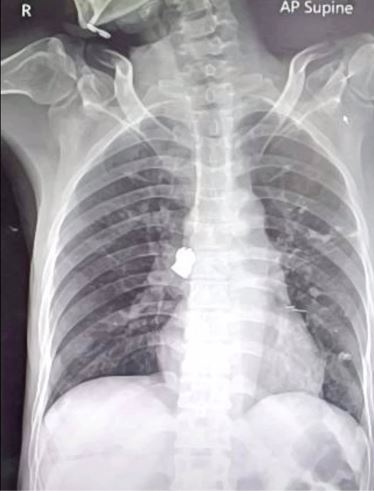

นพ.อนุชิต นิยมปัทมะ แพทย์เฉพาะทางโรคระบบการหายใจและภาวะวิกฤติโรคระบบการหายใจ รพ.มหาราช นครราชสีมา เปิดเผยว่า จากการตรวจเบื้องต้นพบวัสดุของแข็งติดค้างในปอด ผู้ป่วยแจ้งว่าในระหว่างพูดสาบานได้อมพระพิฆเนศ ทำให้พระหลุดเข้าไปในหลอดลม แพทย์ส่องกล้องด้วยพบวัตถุขนาดใหญ่เท่ากับเหรียญบาทเล็กอยู่ในหลอดลมปอดด้านขวา ใช้เครื่องมือพิเศษคีบออกมา ใช้เวลาประมาณ 5 นาที ตอนนี้อาการโดยรวมผู้ป่วยปกติ